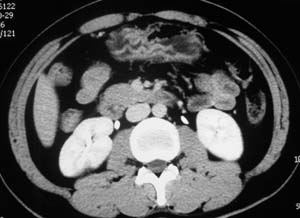

以下是引用子期在2010-3-19 20:47:00的发言:[br]血管畸形的ct增强应该有明显强化,本例并不相符合。本例双肾局部的略低密度影,累及肾盂,局部皮质明显变薄、内陷,增强扫描有轻度的强化,应考虑为炎性病变,患者为年轻男性,累及双肾的感染以结核较常见,可以没有明显的临床症状,尿中有时候也并不能查出什么;肾脓肿常有明显感染中毒症状,本例不符,另外一般的肾盂肾炎或肾小球肾炎通过小便就可确诊,其它还不能排除的是黄色肉芽肿性肾盂肾炎,然而单凭ct一般也很难鉴别。